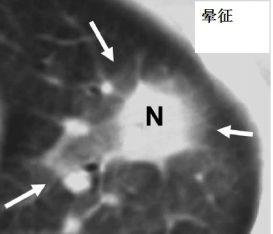

图7-8 胸部CT肺结核、军团菌、巨细胞病毒、肉芽肿、肺癌等有可能形成晕征,但是结合患者免疫力低下,对曲霉菌的特异性还是很高的。

免疫力低下,实变或者结节周围晕征,要高度怀疑血管侵袭性曲霉病。